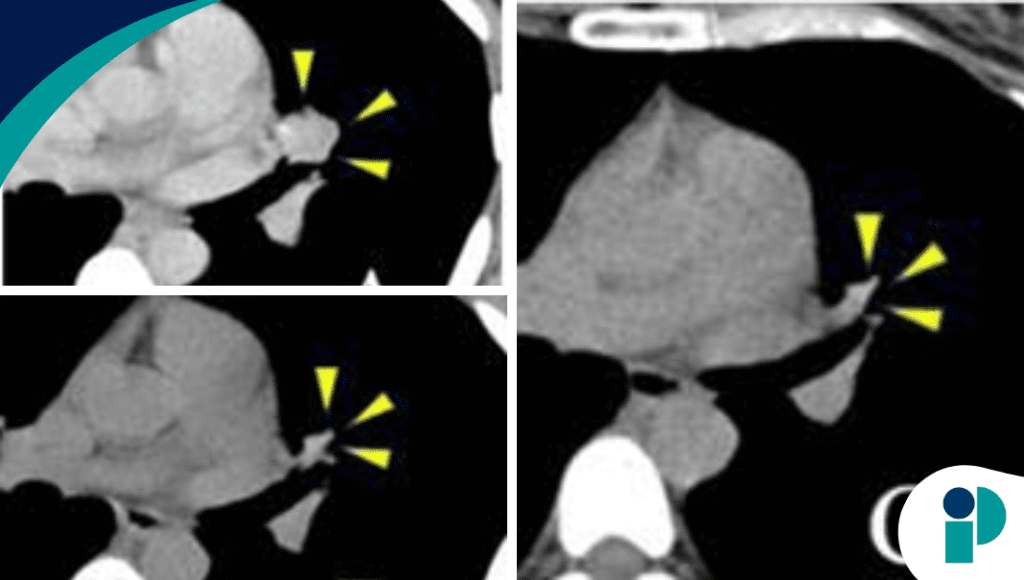

Los estudios genéticos revelaron una alteración molecular específica susceptible a terapia dirigida, un hallazgo clave que permitió replantear la estrategia de manejo. Este tipo de mutaciones, aunque poco comunes, pueden convertirse en blancos terapéuticos altamente efectivos cuando son identificadas a tiempo.

Con base en este hallazgo, se inició tratamiento con una terapia dirigida, logrando respuesta clínica significativa, reducción tumoral y mejoría sintomática. Este resultado resalta el impacto de la medicina de precisión en escenarios donde las terapias estándar han fallado.